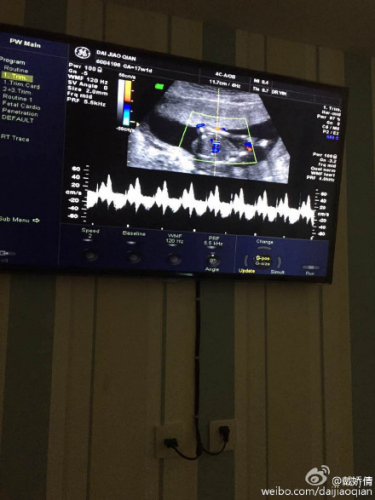

3、这位知友,怀孕四个半月通过B超和彩超就能够分辨出男孩女孩B超单还有一个妙处,就是让B超单告诉你宝宝的性别其一 看数据,如果长和宽的相差在一倍以上男宝宝可能性大长和宽相等女宝宝可能性大其二 看形状,像茄子或长条状的是男宝宝可能性大,圆圆的是女宝宝可能性大17W+1D的BC数据。

4、B超单的神奇作用之一就是可以告诉你宝宝的性别 其一看数据,如果长和宽的相差在一倍以上男宝宝可能性大长和宽相等女宝宝可能性大其二看形状,像茄子或长条状的是男宝宝可能性大,圆圆的是女宝宝可能性大17W+1D的BC数据 胎囊29*19 生的是男孩29W+4D的BC数据 宫内见46。

7、生男生女其实并不重要,只要宝宝健康比什么都好,男孩女孩在饮食上妈妈能够感觉出一点还有就是看b超单其一 看数据,如果长和宽的相差在一倍以上男宝宝可能性大长和宽相等女宝宝可能性大其二 看形状,像茄子或长条状的是男宝宝可能性大,圆圆的是女宝宝可能性大17W+1D的BC数据 胎囊。

11、b超单子x和y的标志来判断男女 1看肾盂分离,肾盂分离指的是肾脏和输尿管并不是紧密相连的,而是有一定的距离,如果在b超单子上判定为肾盂分离,那么很可能是因为男孩常在肚子中憋尿导致的,通过分离的程度这一项就能作为y染色体的标志,即怀的是男孩 2看股骨长度,从双顶径和股骨长的差值来判断生男生女更为可。

12、数据是胎儿身体的各种数据,比股骨的长度,双顶径等,其实通过B超这些数据,只能反映出胎儿的身体发育情况,无法推测出胎儿到底是男孩还是女孩,所以千万不要相信可以通过B超数据看出男女的说法,更不要因为B超数据上的推测就自己决定是否放弃胎儿所以说通过B超数据看男女是不准确的,也是无法看出的,最好是。